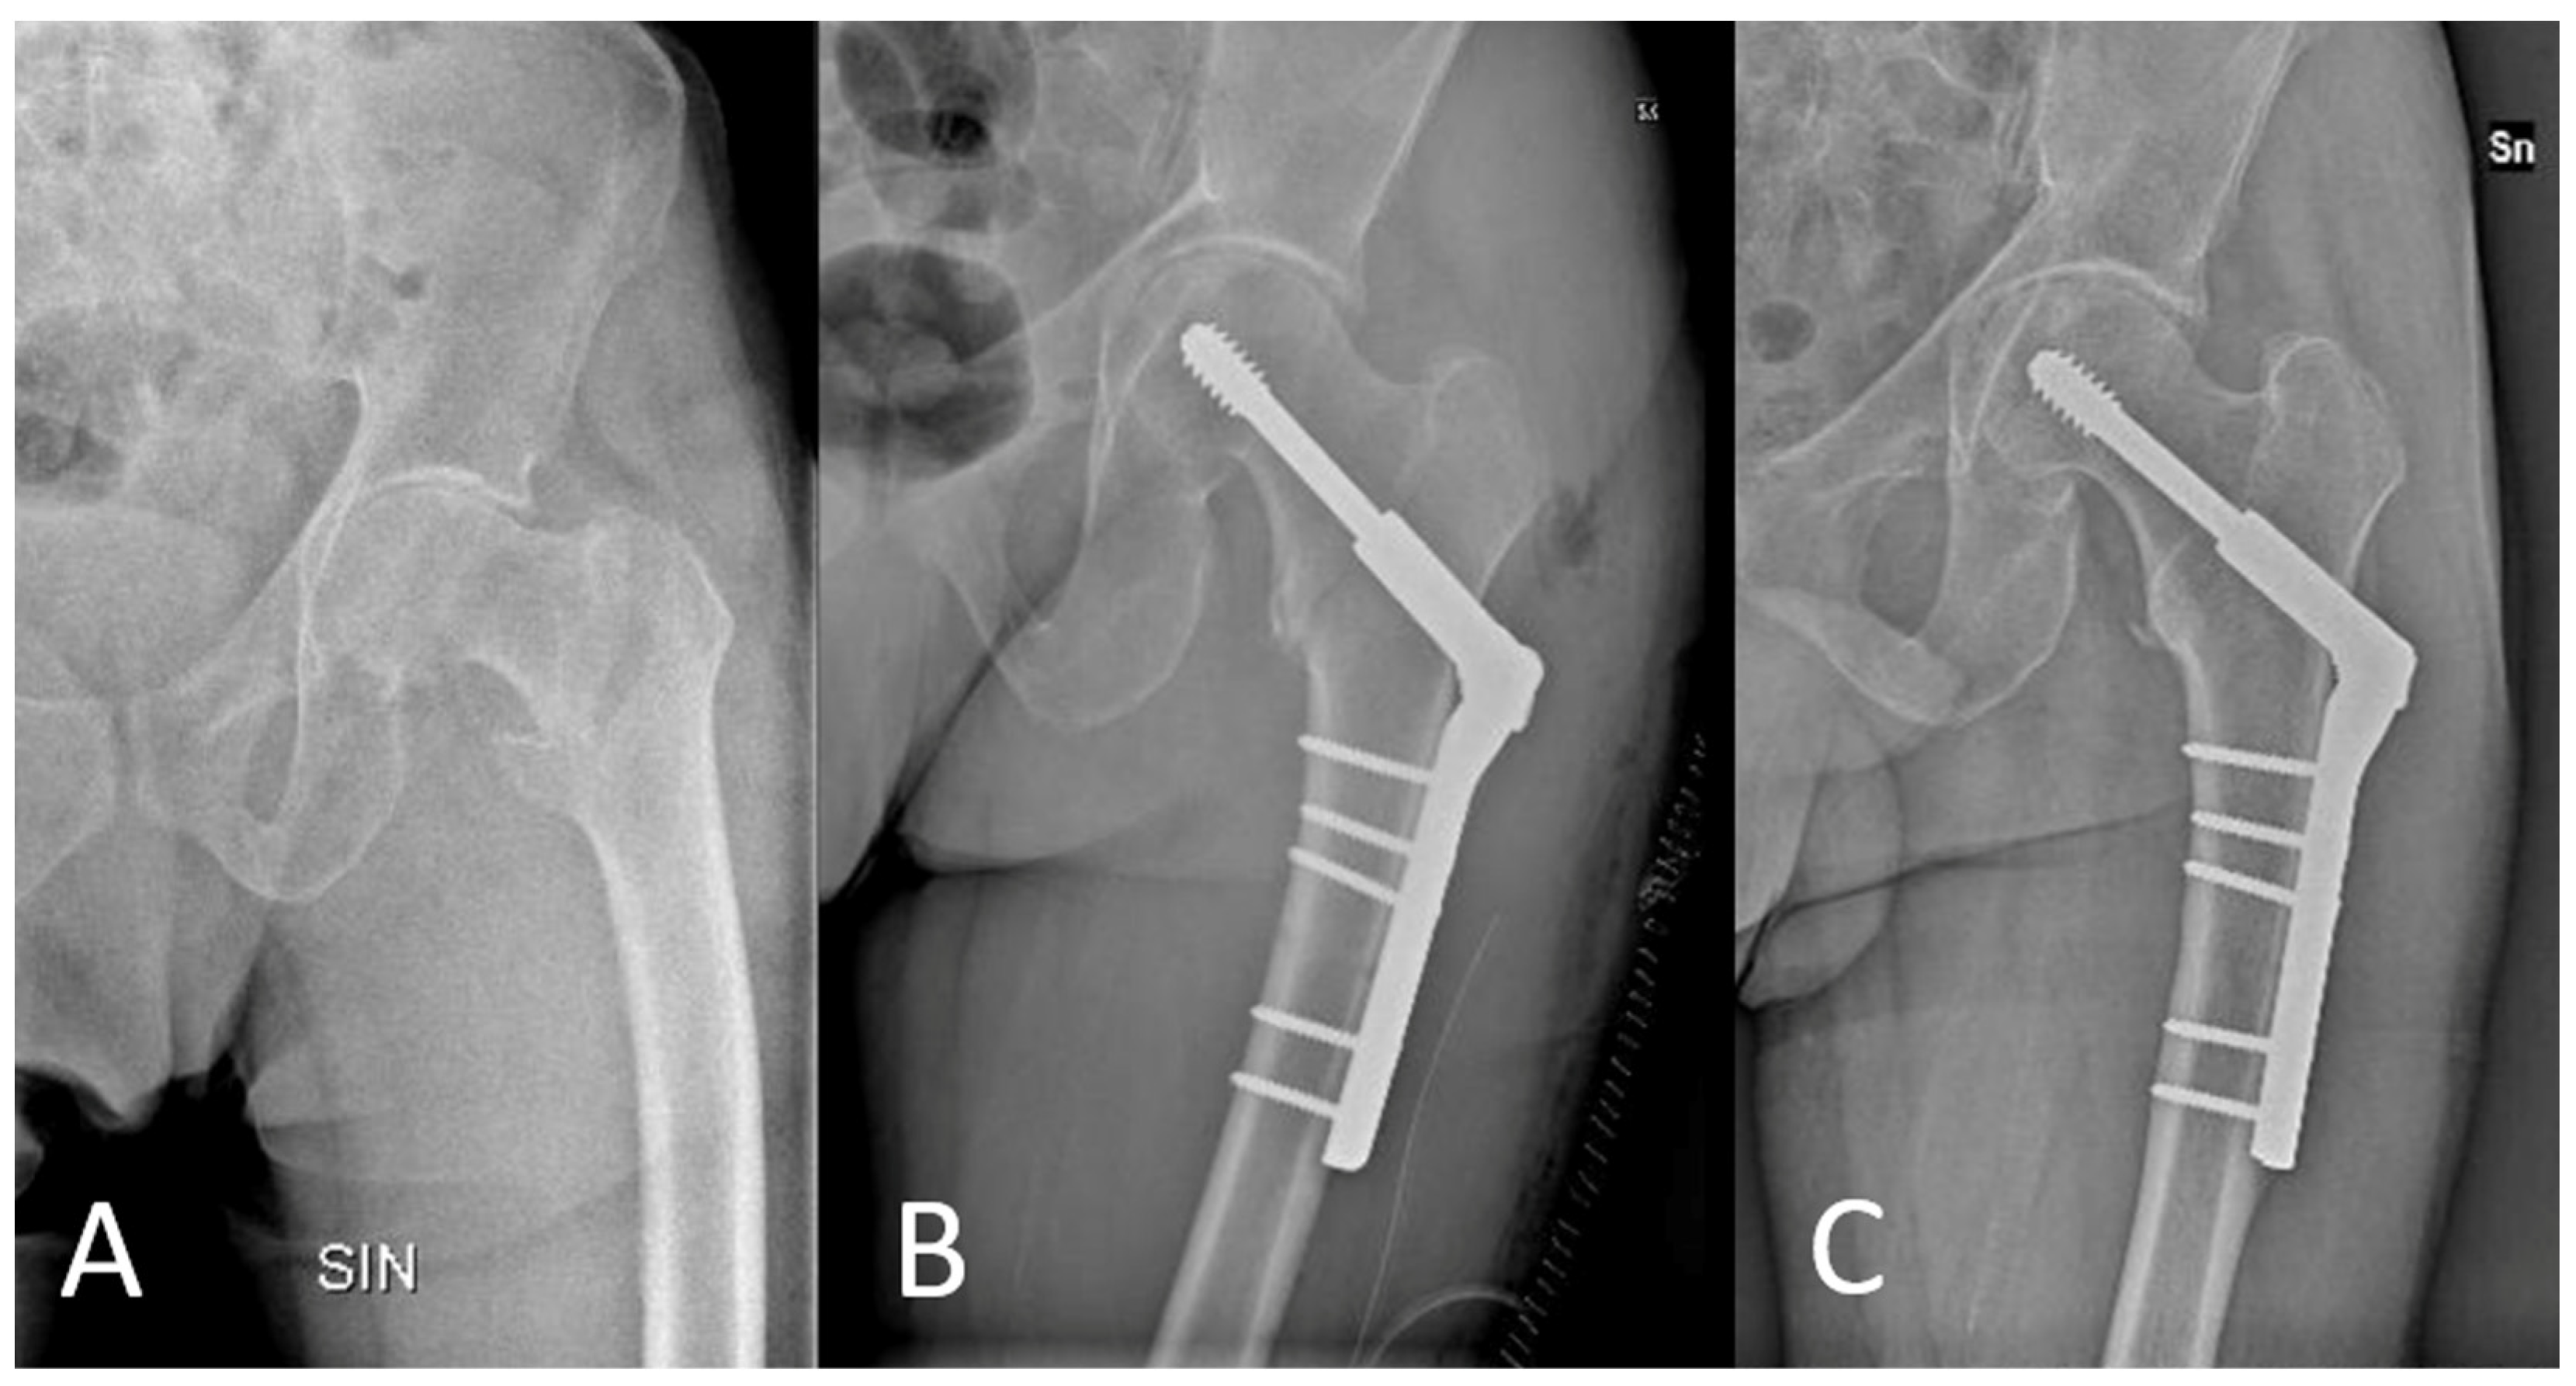

Angle-Adjustable Dynamic Hip Screw Plate for Unstable Trochanteric Fractures in Middle-Aged Patients: Mid-Term Outcomes and Return to Sport

2.1. Surgical Technique